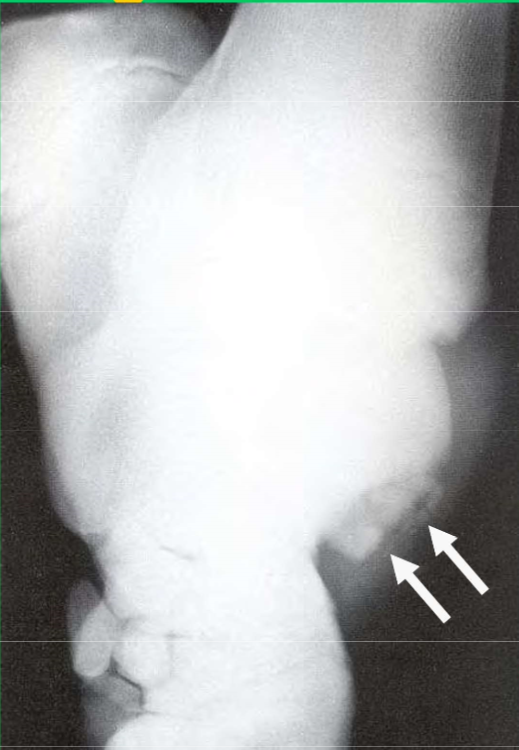

What is this lesion

OCD of the distal intermediate ridge of the tibia in the hock